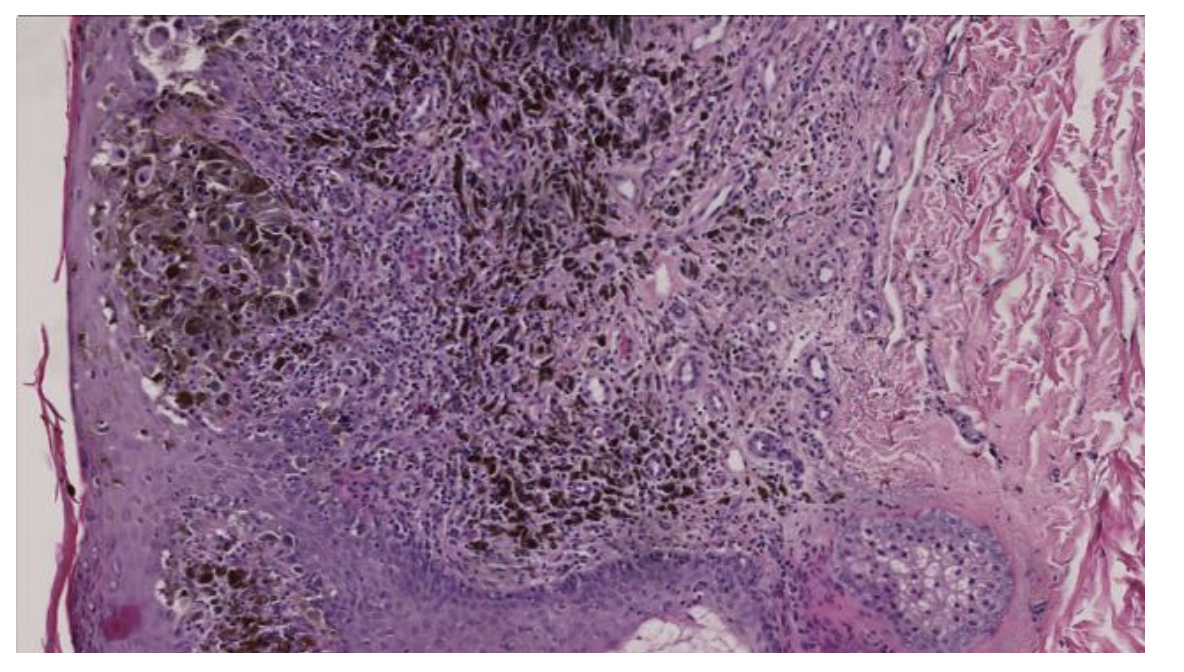

Det mikroskopiske billede fra colon viser

a. Hyperplastisk polyp

b. Adenom med let dysplasi

c. Adenom med svær dysplasi

d. Colitis ulcerosa

e. Adenokarcinom

*e. Adenokarcinom